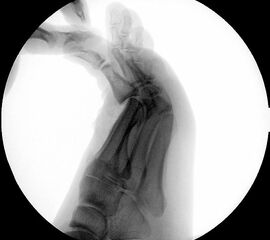

Klinisch zeigt sich stadienabhängig eine schmerzhafte Bewegungseinschränkung mit zunehmender Steifigkeit des Großzehengrundgelenkes. Vor allem die Einschränkung der Dorsalextension wird von den Patienten oft als unangenehm empfunden. Initial besteht eine bindegewebige Alteration im Gelenk, im weiteren Stadium treten Knorpeldegeneration und Begleitsynovialitis mit der Ausbildung von osteophytären Randanbauten auf. Klinische treten diese meist durch eine schmerzhafte dorsale Knochenkante in Erscheinung (Abbildung 1).

Im späten Stadium imponiert eine Gelenkblockierung durch freie Gelenkkörper. Während in den Anfangsstadien vor allem die dorsalen Anteile des Gelenks betroffen sind, betreffen die Veränderungen in den Fortgeschrittenen Stadien die gesamte Zirkumferenz einschließlich des Sesambeingleitlagers. Im Endstadium kommt es zu einer weitgehenden Ankylosierung des 1. Metatarsophalangealgelenks.